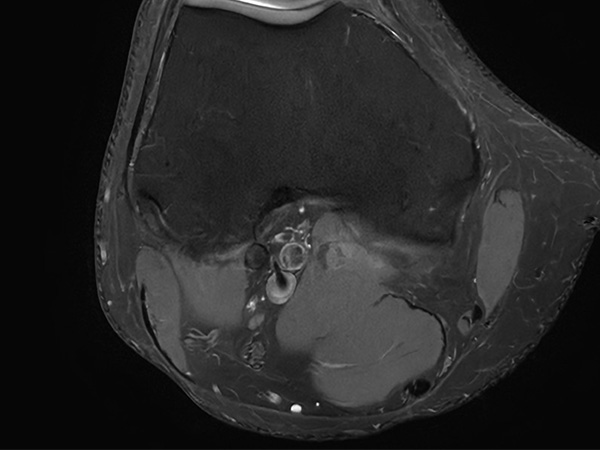

Fast Knee imaging with SmartSpeed Precise